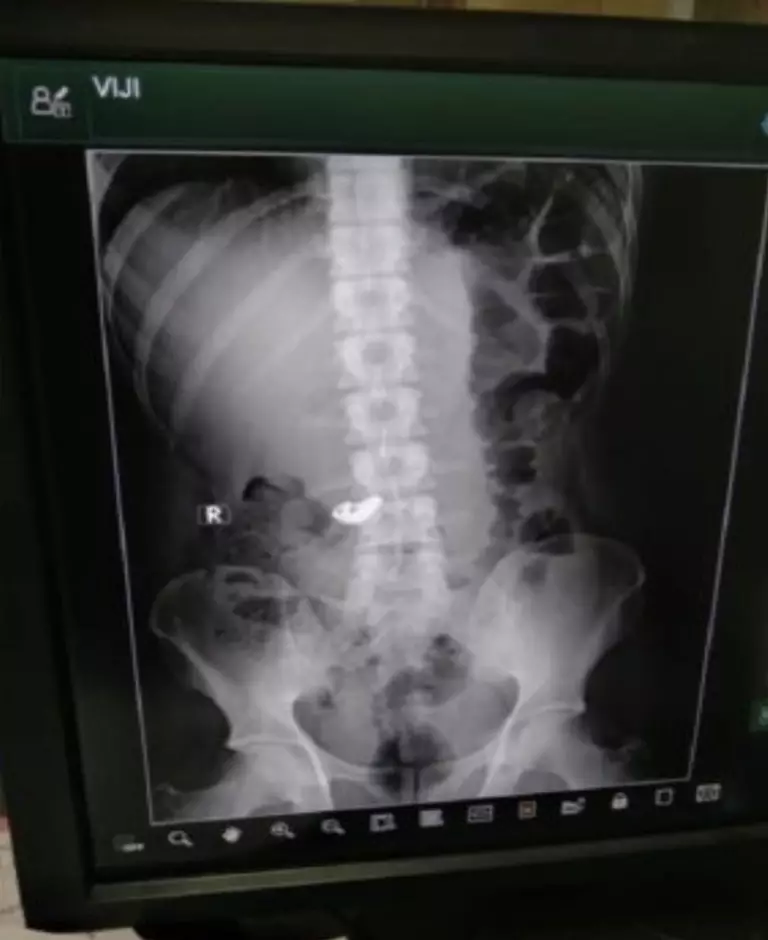

Pencuri emas ini kemudian dibawah ke kantor polisi terdekat. Inspektur BG Kumaraswamy mengirimnya ke rumah sakit terdekat agar luka-lukanya bisa diobati. Aksi Vijay yang menelan rantai emas itu ketahuan setelah dokter melakukan pemindaian X-Ray pada tubuhnya.

Potongan emas itu sudah berada di dalam perut Vijay. Akan tetapi ia mengaku bahwa benda yang ada di perutnya bukan emas melainkan hanya tulang yang tertelan. Petugas tetap meminta Vijay makan pisang agar rantai emas tersebut keluar dari perutnya.